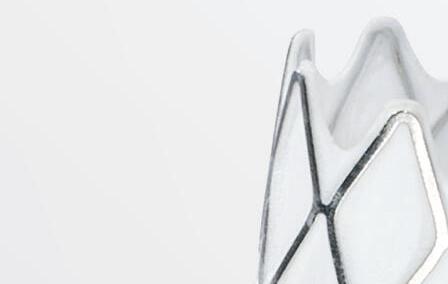

Endovascular interventions for chronic limb-threatening ischemia (CLTI) are technically demanding endeavors. Multi-level arterial disease, long-length lesions and other complex plaque characteristics are frequently encountered when treating these patients.1,2 Calcium modification with intravascular lithotripsy (IVL) has emerged as a useful tool to combat the challenges of calcified lesions with the goal of maximizing luminal gain to achieve improved endovascular outcomes, both radiographically and clinically.3 Balanced lithotripsy pulse delivery across longer-length lesions, as well as effectively treating calcified disease across multiple arterial beds, can be laborious considering the number of available pulses and the length of the IVL catheter relative to the extent of disease.

To address this, the Shockwave IVL peripheral portfolio has now been enhanced with the addition of the Shockwave E8 catheter. The Shockwave E8 contains eight emitters across an 80mm-length balloon platform with treatment diameters ranging from 2.5–6mm and the ability to deliver up to 400 pulses. A working length of 150cm now provides an extended reach for more distal disease. The Shockwave E8 catheter allows for expanded application of IVL in treating a wide range of infrainguinal disease. Longer-length lesions involving the superficial femoral (SFA) and popliteal arteries or disease involving multiple tibial arteries that may have previously required a very selective pulse delivery approach can now be more broadly treated with the Shockwave E8.